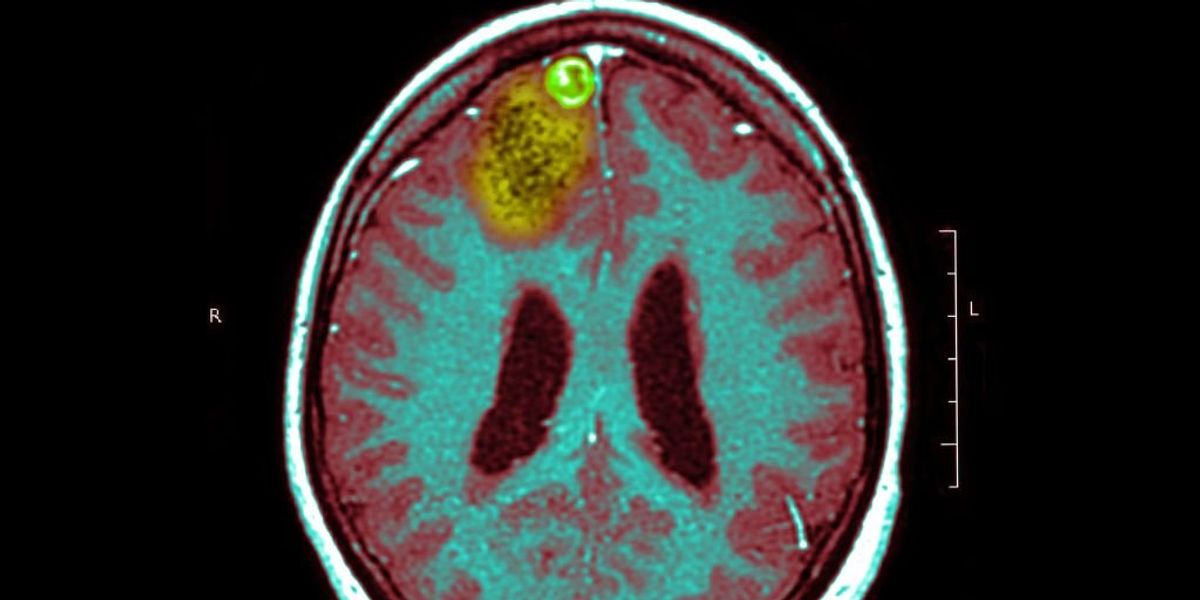

of mayo clinic Glioblastoma is defined as:

A type of cancer that begins as a growth of cells in the brain or spinal cord. They multiply rapidly and can invade and destroy healthy tissue. Glioblastomas form from cells called astrocytes, which support nerve cells. Glioblastoma can occur at any age. However, it tends to occur more often in older people and occurs more often in men. Symptoms of glioblastoma include a headache that keeps getting worse, nausea and vomiting, blurred or double vision, and seizures.

Scoria, a 57-year-old married father of three, was diagnosed with a brain tumor last June.

Scolier, his family and treatment team were extremely nervous when it came time for his latest brain scan at the end of January.

Long said his friend’s brain was “normalizing”.

“I’m excited,” said Scoiler, “My glioblastoma, which is supposed to be incurable, hasn’t come back!”